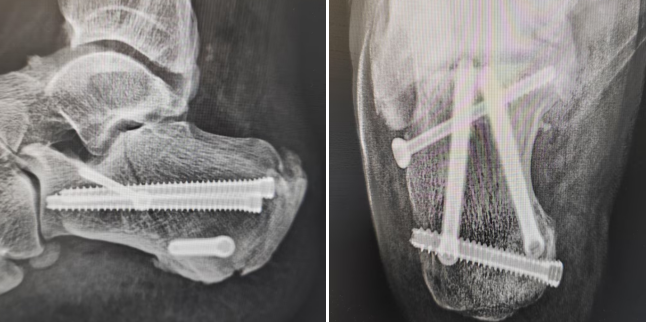

(术后)